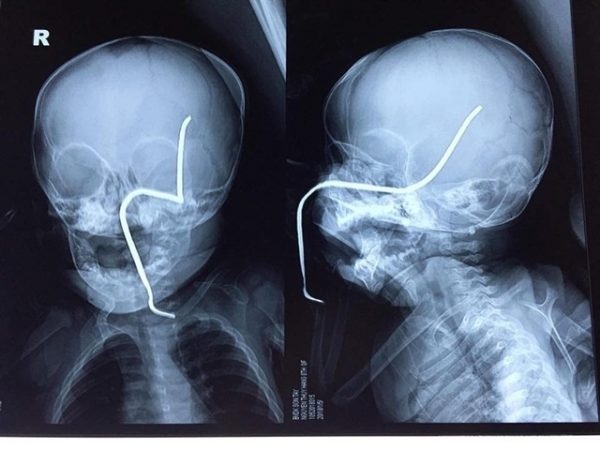

Ngày 30/7, Bệnh viện Trẻ em Hải Phòng cho biết nơi đây vừa cấp cứu thành công cho bé trai 6 tuổi, bị thanh sắt dài 60 cm, đường kính 2 cm găm vào người. Bệnh nhi là N.H.N.M., ở huyện An Dương, Hải Phòng.

Chiều một ngày trước, M. được gia đình đưa đến bệnh viện trong tình trạng tỉnh táo. Tuy nhiên, ở khu vực bộ phận sinh dục của em có một thanh sắt xuyên lên phía ổ bụng.

Bác sĩ Nguyễn Duy Tâm cho biết đây là trường hợp cấp cứu hy hữu. Bé bị thanh sắt đâm xuyên người nhưng kết quả siêu âm, X-quang và CT đều cho thấy ổ bụng không tổn thương nghiêm trọng; động mạch chủ và tinh hoàn không vỡ.